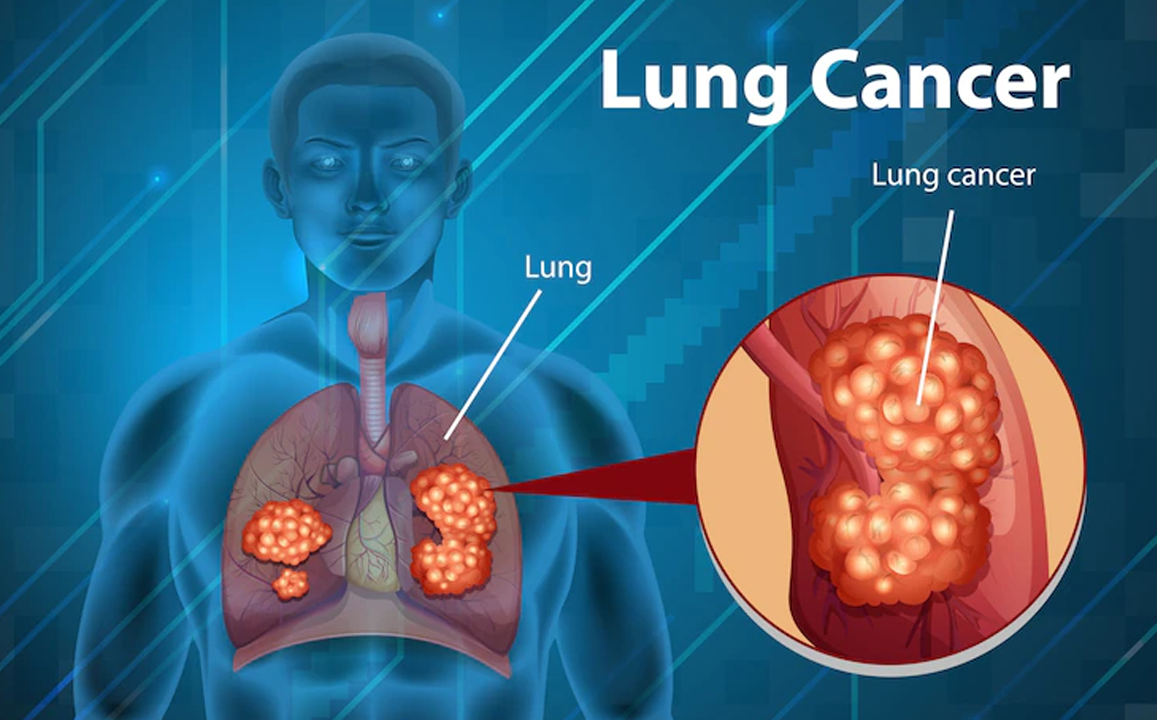

Lung Cancer

Lung cancer is a disease where abnormal cells in the lungs grow uncontrollably, forming tumors that impair lung function.